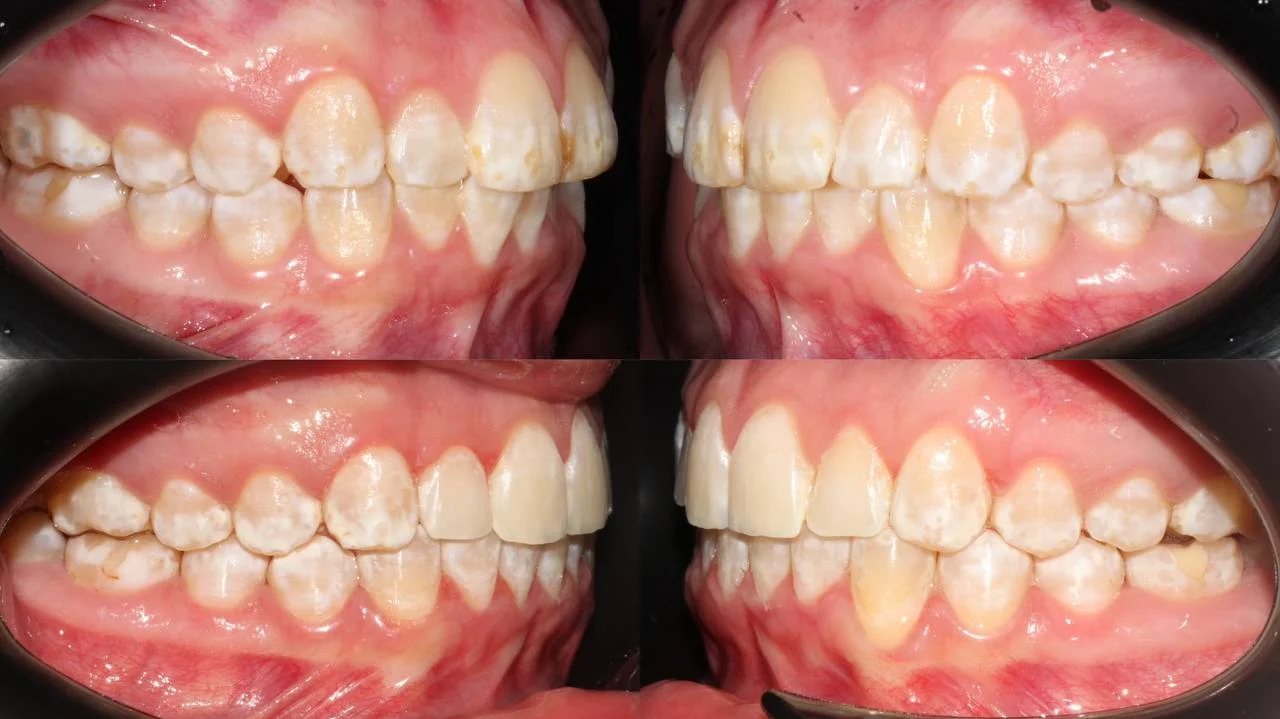

Нарушение соотношения челюстей и неправильное положение зубов — зубные ряды смыкались некорректно, зубы стояли со смещением.

Проблема: Пациентку не устраивало положение зубов и то, как смыкаются челюсти. Зубы стояли неровно, ряды сходились неправильно.